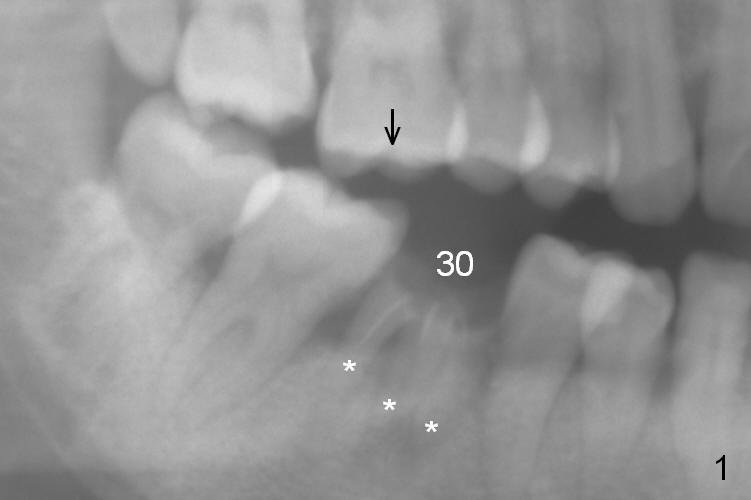

A 37-year-old woman is afraid of dentistry and procrastinates implant restoration at #30 (Fig.1).  The opposing tooth is supraerupted (arrow) and warrants occlusal adjustment for #30 immediate provisional.  Since there are 3 roots associated with #30 (*), the septum should be tripod, where osteotomy will be established after Clindamycin socket application.  Primary stability of the immediate implant is further enhanced by the bone height.  It is expected to gain ~ 6 mm in the native bone (Fig.2 blue line).  As long as the osteotomy is slightly longer than the 2nd molar, there is minimal chance to involve the superior border of the Inferior Alveolar Canal (red dashed line).  Magic Split and Expanders are to be used in combination with drills if necessary.  Photograph the septum before and after osteotomy.